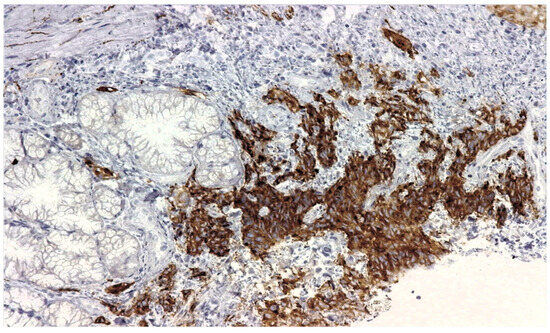

2. Detailed Case Description

2.1. Diagnostic Evaluation